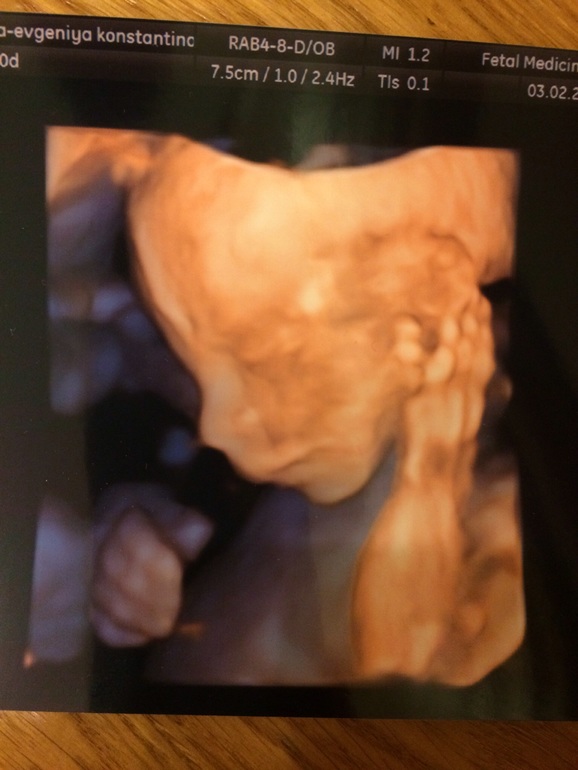

Детка здорова, самое главное! Осмотрели тщательно каждую косточку, пальчики, ушки, хрусталики глаз, внутренние органы. Лежит вниз головкой, в пуповине не запуталась.

И, конечно, новость! Врач подтвердил наши ожидания с 18 недель - ждем с середины июня Григория Максимовича! :-)) УРА-УРА! Мы безумно с мужем хотели первого сына. Очень бы обрадовались доче, но сын - это какой-то совсем особый космос! Маленький мужчина! В некотором смысле, у меня теперь есть яйца. Ну, посмотрите, какой еще кроха (381 г намерили), а уже деловой, по мобиле вопросы решает:

Очень похож на мужа даже в 20 недель, сынище наш :-) Ждем следующего скрининга!